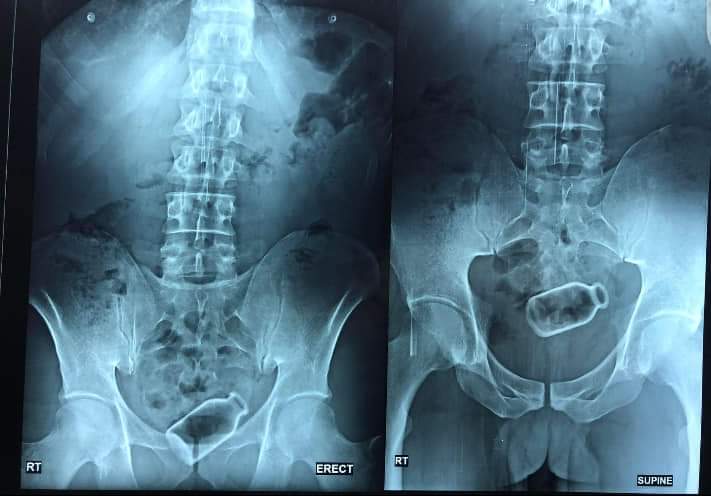

وعقلت على واقعة استخراج زجاجة دواء من قولون مريض، قائله: “زجاجة الدواء التي أدخلها المريض إلى جسده كان من الممكن أن تحدث ثقب بالقولون”.

وكشفت الدكتورة أسماء جميل، استشاري الجهاز الهضمي بكلية الطب جامعة المنصورة، عن أغرب الحالات التي تقوم بعلاجها أو إجراء عمليات جراحية لها، وهي استخرجها زجاجة الدواء من بطن مريض، أوضحت أن المريض يبلغ من العمر 38 عامًا، وابتلع الزجاجة لتوسيع مجرى المعدة، ثم استقرت الزجاجة في القولون، معقبه: "الزجاجة كانت على بعد 25 سنتي من فتحة الشرج".